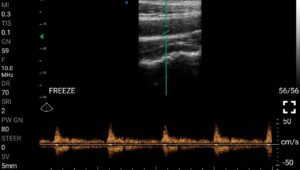

Παραδείγματα

Ολες οι παραπάνω απεικονιστικές εξετάσεις έχουν ληφθεί από φορητή συσκευή όπως: Apple Iphone, Tablet, Samsung Mobile Phones και διάφορες άλλες φορητές συσκευές.